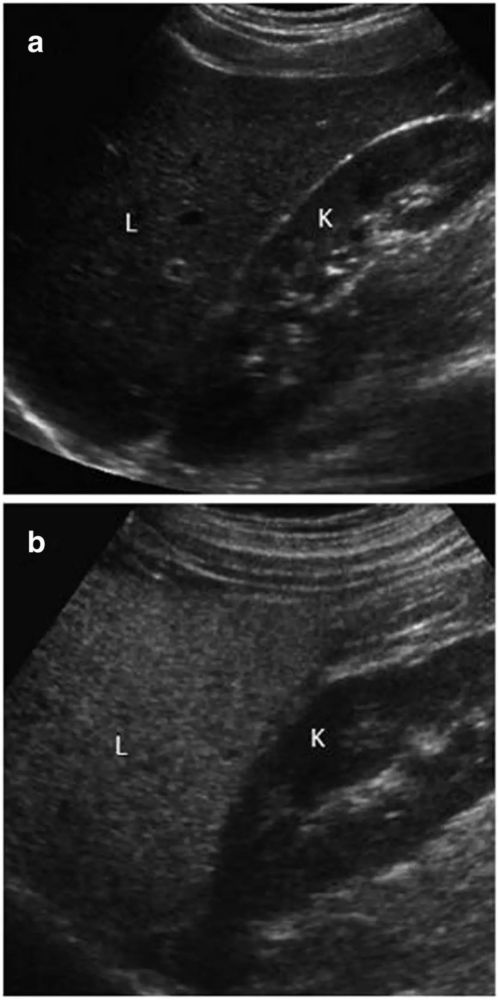

影像学对于瘦型和肥胖型NAFLD的诊断没有区别 。 在超声检查中 , 脂肪囊泡在细胞内蓄积导致肝实质反射增强 , 因此脂肪变性表现为肝脏回声弥漫性增强或“明亮肝”(图1) 。

图1肝脂肪变性的超声评估

a正常肝脏的超声图像显示肝实质(L)和肾皮质(K)的回声相似;b脂肪变性肝脏的超声图像显示肝实质(L)回声增强 , 明显比肾皮质(K)明亮